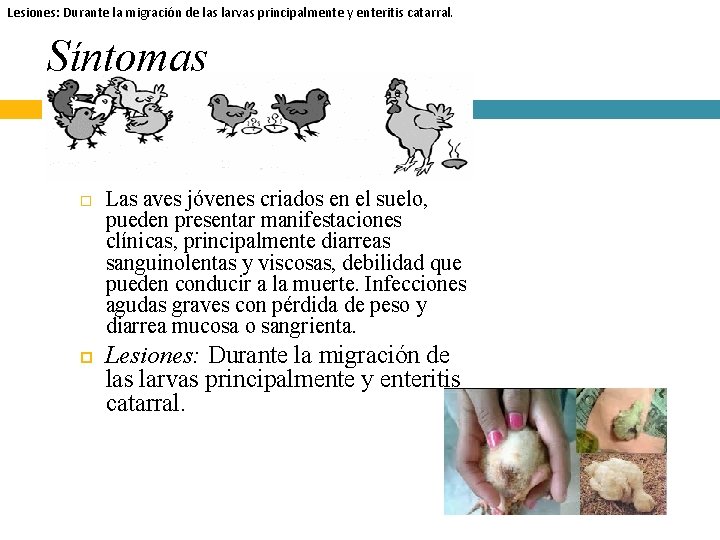

Lesiones: Durante la migración de las larvas principalmente y enteritis catarral. Síntomas Las aves jóvenes criados en el suelo, pueden presentar manifestaciones clínicas, principalmente diarreas sanguinolentas y viscosas, debilidad que pueden conducir a la muerte. Infecciones agudas graves con pérdida de peso y diarrea mucosa o sangrienta. Lesiones: Durante la migración de las larvas principalmente y enteritis catarral.